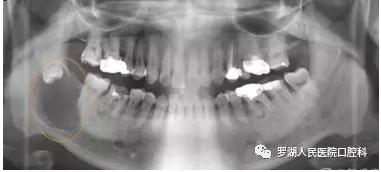

引起牙源性囊肿及肿瘤。

下颌智齿拔掉后,上颌智齿会伸长,进食或说话时会咬到下颌的牙床引起粘膜的溃烂。